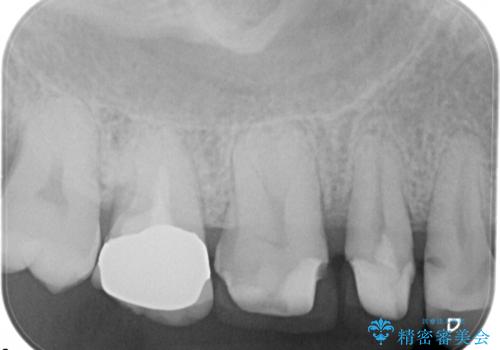

- 定期検診にて不良補綴物、及び虫歯を認めオールセラミッククラウンにて治療を行いました。

右上第二小臼歯はカリエス除去中に露髄を認め、部分的断髄法にて歯髄を保存しております。